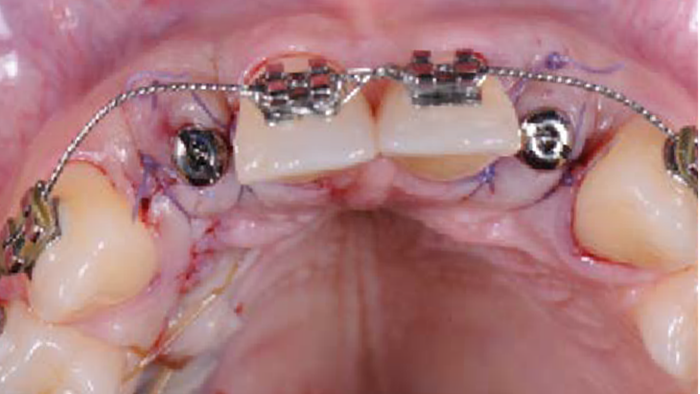

Clinical case: Patient-centered approach: treatment strategy for Root Membrane Technique & delayed implant placement

- Courtesy of Dr. Yoshiharu Hayashi, Japan -

Socket Shield Technique, anterior esthetics, maxillary anterior, esthetic, esthetics, delayed implant placement, socket preservation, AnyRidge, Root Membrane Kit, Root Membrane Technique, Partial Extraction Therapy, PET, esthetic zone, fuse abutment, Dr. Yoshiharu Hayashi,#11,#21,#22

AnyRidge implant system, fuse abutment Root membrane kit, PET Kit